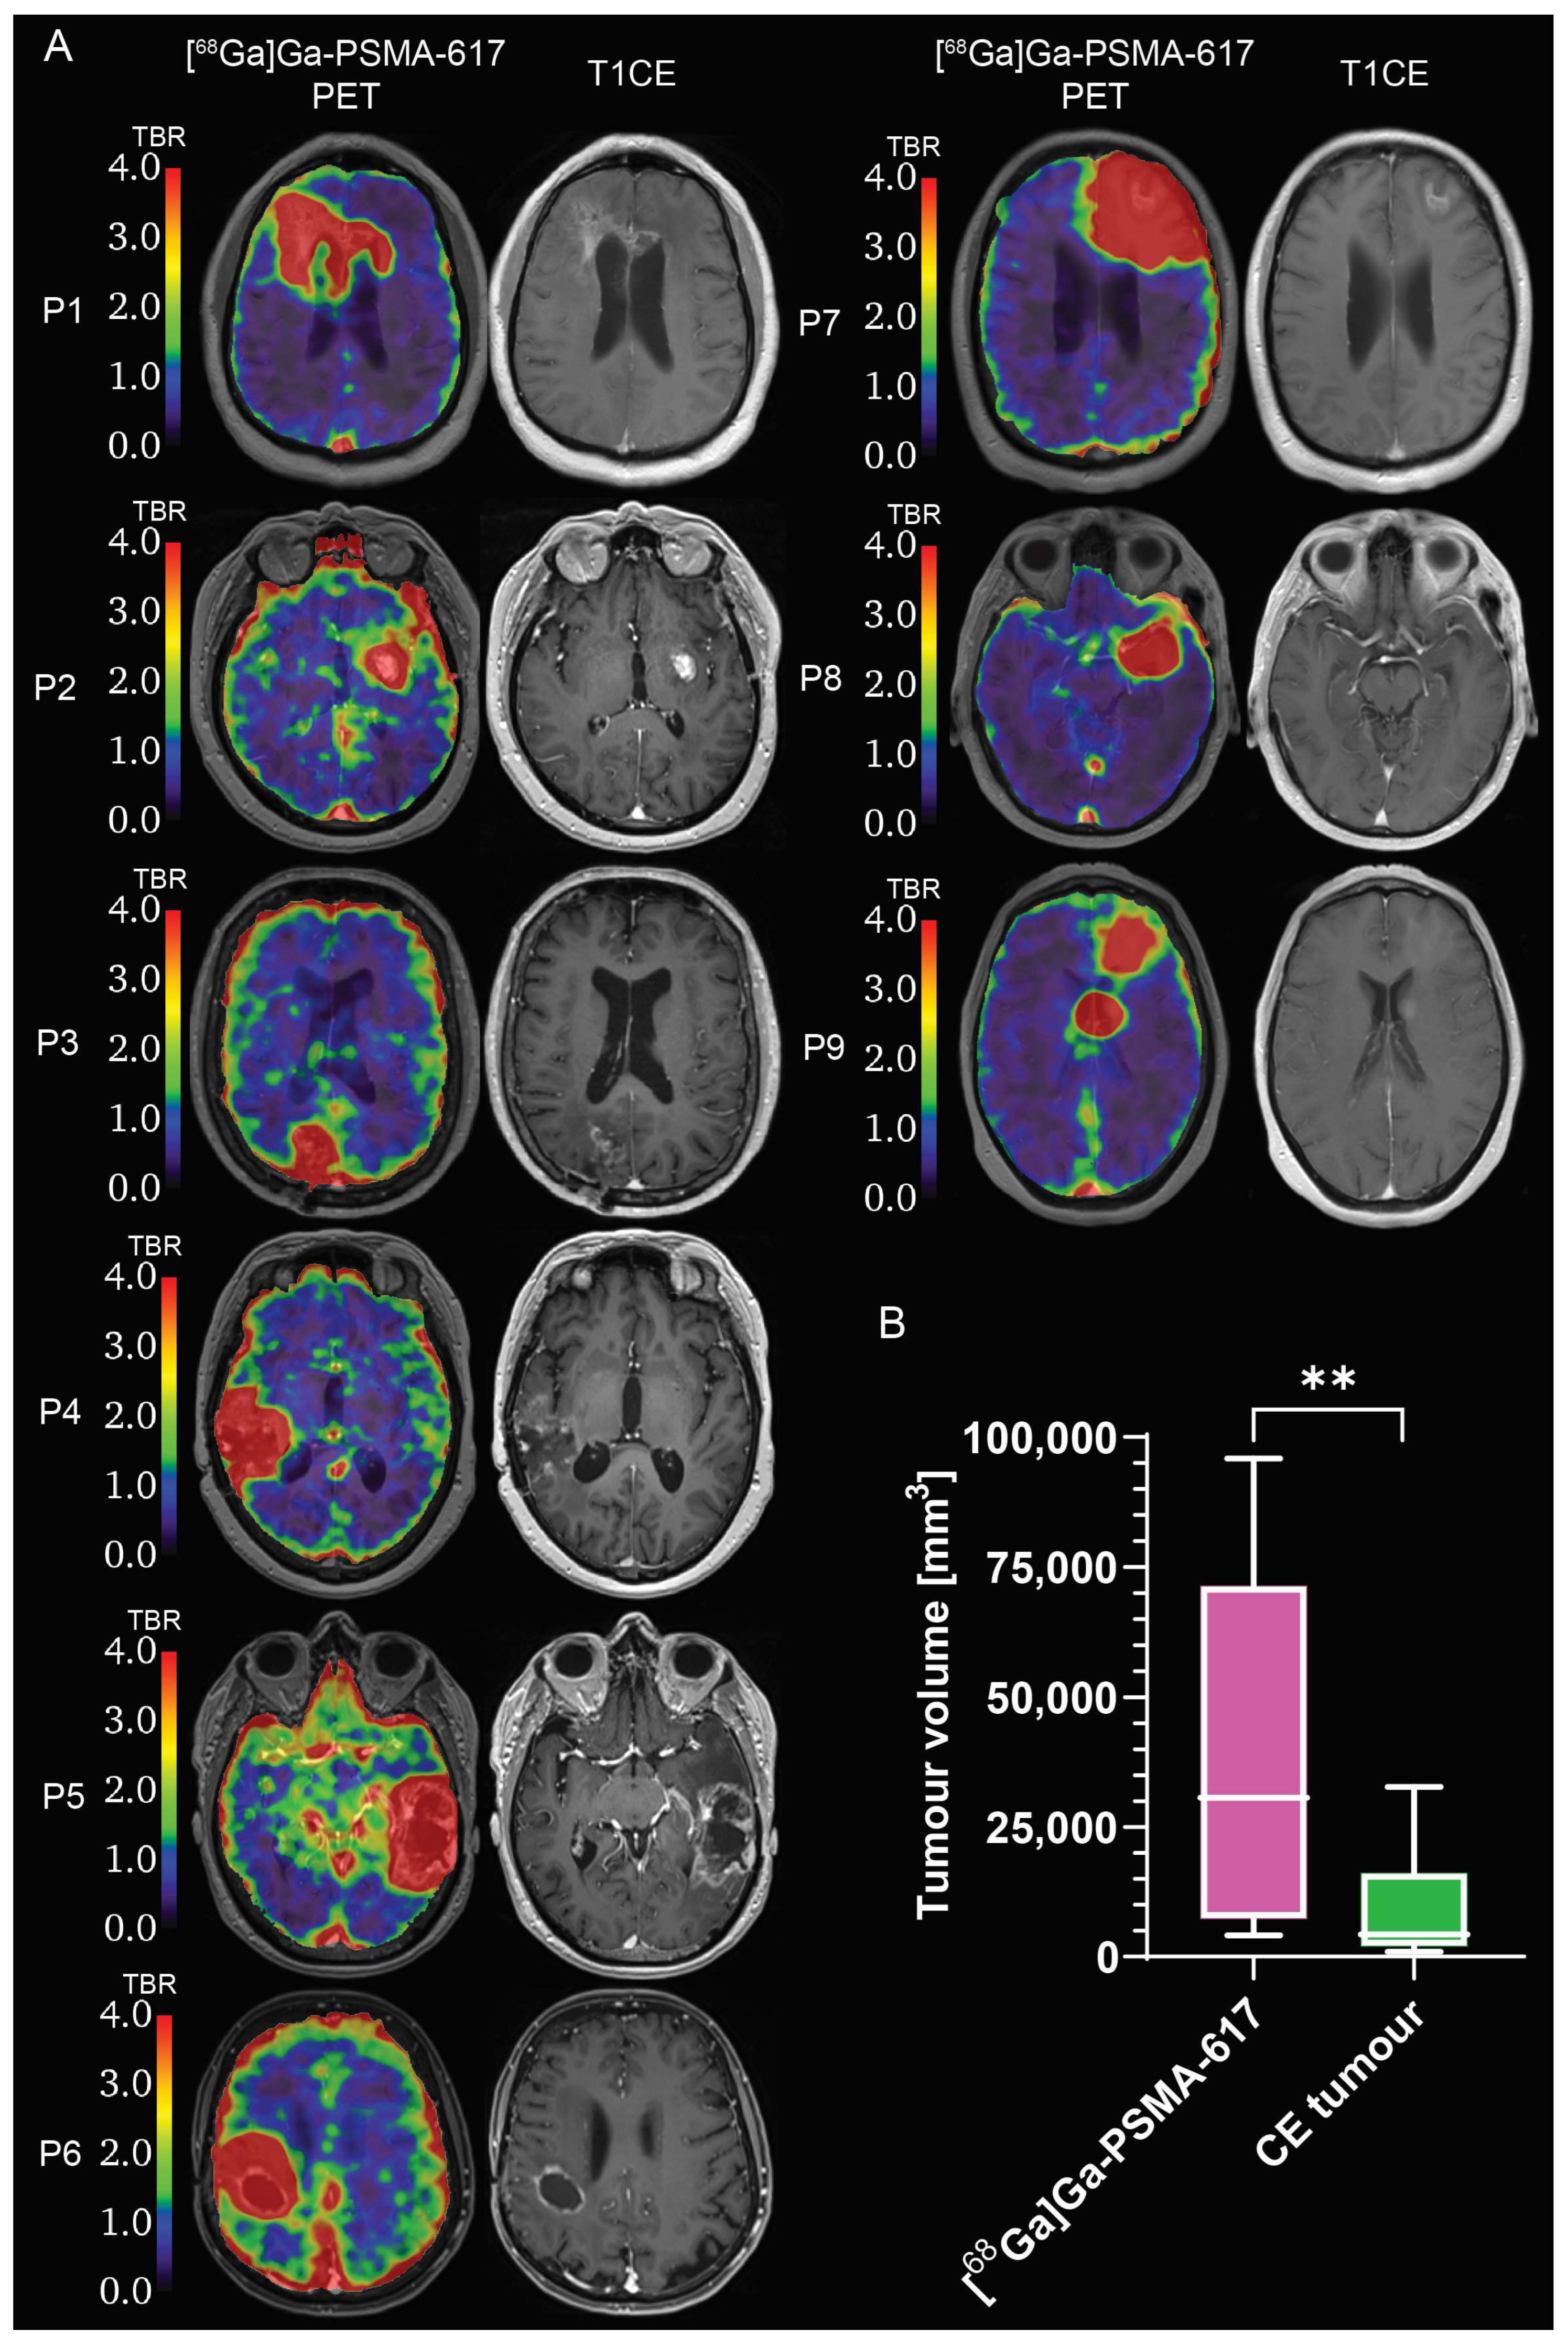

2.2. Evaluation of [68Ga]Ga-PSMA-617 Tumour Selectivity

2.4. Evaluation of [68Ga]Ga-PSMA-617 Potential for Theranostics Application